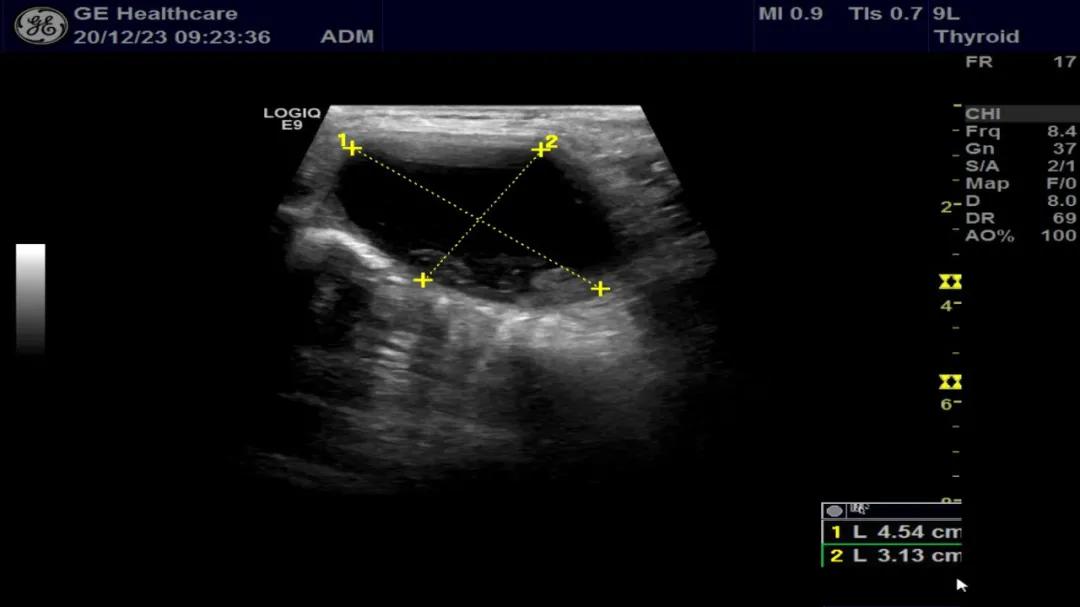

李先生经常规超声检查发现,甲状腺左叶可见两个囊性回声,大小分别约4.5×3.1cm和5.3×3.6cm,内见点絮样中等回声。为进一步确认囊性包块内是否有实性成分,医生为李先生做了遂行超声造影检查,发现均无造影剂填充,其内絮样回声考虑为囊肿内积血。